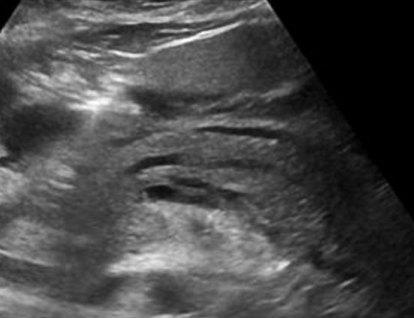

Describe this image

Diagnosis?

Transverse image of pancreas

Pancreatic parenchyma appears hyperechoic with echogenic foci (calcifications) throughout.